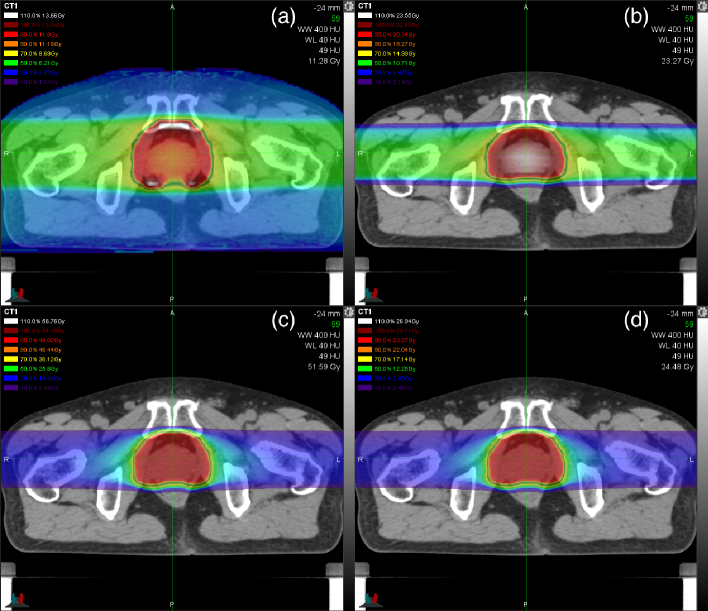

Figure 4 shows the dose distributions calculated for the actual prostate-cancer treatment. The dose-mean -ratio and physical-dose distributions were gentle in the opposing beam arrangement while the ratio was high in the anterior and posterior sides of the prostate and the physical dose was high in the central prostate. The relative difference between the clinical dose in figure 5(c) and the ERD in figure 5(d) was minor due to small quadratic-term contribution at the level of 4.3 Gy (C) or 1.78 Gy (RBE) as consistent with figure 3.

Figures 5(a) and 5(b) show the profiles of total physical dose and dose-mean ratio, where the two opposing beams were designed for 12 fractions of 4.3 Gy (C) and were also reused for the hypofractionated treatment plans with rescaling to conserve the ERD to the point with . The RWD distribution in figure 5(c) was severely deformed with hypofractionaton, while the ERD distribution in figure 5(d) was nearly invariant, so that the plans of different fractionation cannot be compared with RWD even relatively. The degradation of the SOBP with hypofractionation was apparently caused by the forced reuse of the nonopimal beams in this analysis. In the outside of the SOBP in figures 5(e) and 5(f), the alternate beam delivery increased the RWD and ERD themselves and the influence of hypofractionation on ERD.